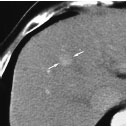

RFA术前对比增强CT示2.0 cm×2.0 cm肝细胞癌

RFA术后30分钟对比增强CT动脉相示低衰减的卵圆形消融带(射频消融技术成功的标志)